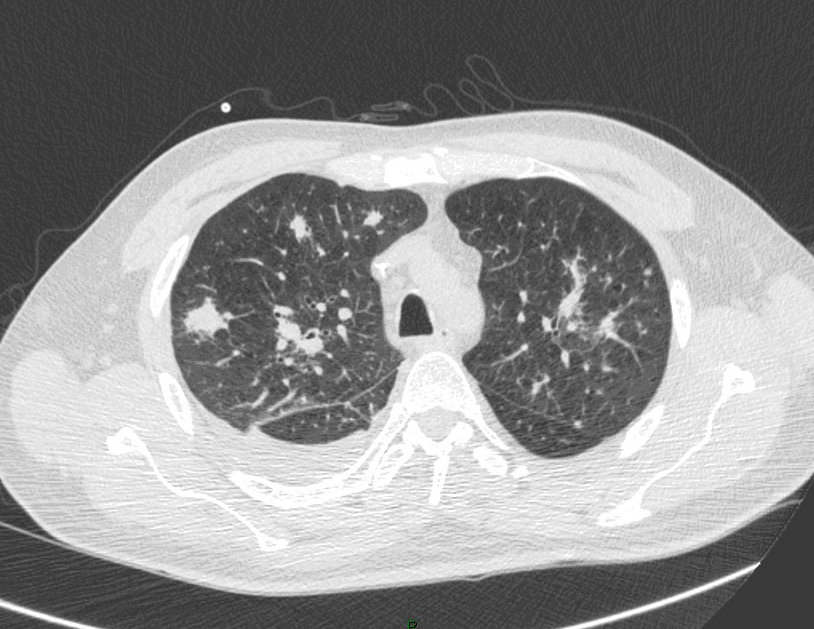

La fièvre persiste malgré les antibiotiques. Cela fait maintenant 5 jours, et vous décidez donc de réaliser un scanner thoracique dont les images sont les suivantes.

Question 13 : Comment décrivez-vous ces images ?

Nodule pulmonaire entouré de verre dépoli

Hypothèse la plus probable devant le terrain de neutropénie prolongée et les images en faveur

Aspergillose pulmonaire invasive = infection fongique invasive la plus fréquente chez le patient avec neutropénie prolongée (> 7 jours de neutropénie).

- imagerie :

°précoce : signe du halo : nodule unique ou multiple, avec verre dépoli autour (signe du grelot se voit dans l’aspergillome compliquant une caverne tuberculeuse par exemple) ;